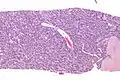

| Micrograph of an adenomyoepithelioma. H&E stain. | |

An adenomyoepithelioma of the breast is a rare tumour in the breast composed of glandular elements (adeno-) and myoepithelial cells. It is usually benign;[1] however, there are reports of malignant behaviour.[2]

The histomorphologic appearance can mimic invasive ductal carcinoma, the most common type of invasive breast cancer.